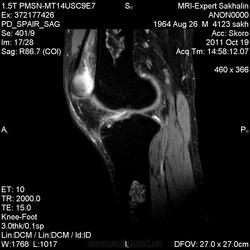

- В ранней стадии заболевания - отек (гипоинтенсивный на Т1-взвешенном изображении и гиперинтенсивный на Т2-взвешенном изображении)

- Позднее отграничение вдоль периферии пораженной кости (гипоинтенсивное на Т1 - взвешенном изображении; на Т2-взвешенном изображении - гиперинтенсивная линия по направлению к зоне некроза, соответствует грануляционной ткани)

- Гипоинтенсивная линия по направлению к здоровой кости (склероз, фиброз): признак двойной линии

- Накопление контрастного вещества периферической зоной

- При застарелых инфарктах кости интенсивность сигнала зоны некроза эквивалентна жировой ткани

- Периферическая зона типично извилистая, напоминает гирлянду.

а, b Инфаркт зрелого костного мозга. (а) Сагиттальная протонная плотно-взвешенная МРТ с подавлением МР-сигнала от жировой ткани. Изображение демонстрирует гирляндовидный склеротический край и центральный участок с сигналом жирового костного мозга. Множественные некротические зоны расположены преимущественно в метадиафизальной области, однако несколько находятся непосредственно рядом с суставом, в связи с чем имеется риск уплощения суставных поверхностей;